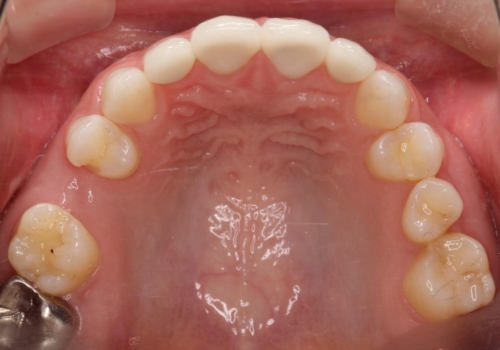

インプラント埋入手術は1回で全て行い、2ヶ月後にはセラミック治療で、審美回復と機能回復をしました。

来院回数が少なく、しっかり食事もできるとの事で非常に喜んで頂けました。